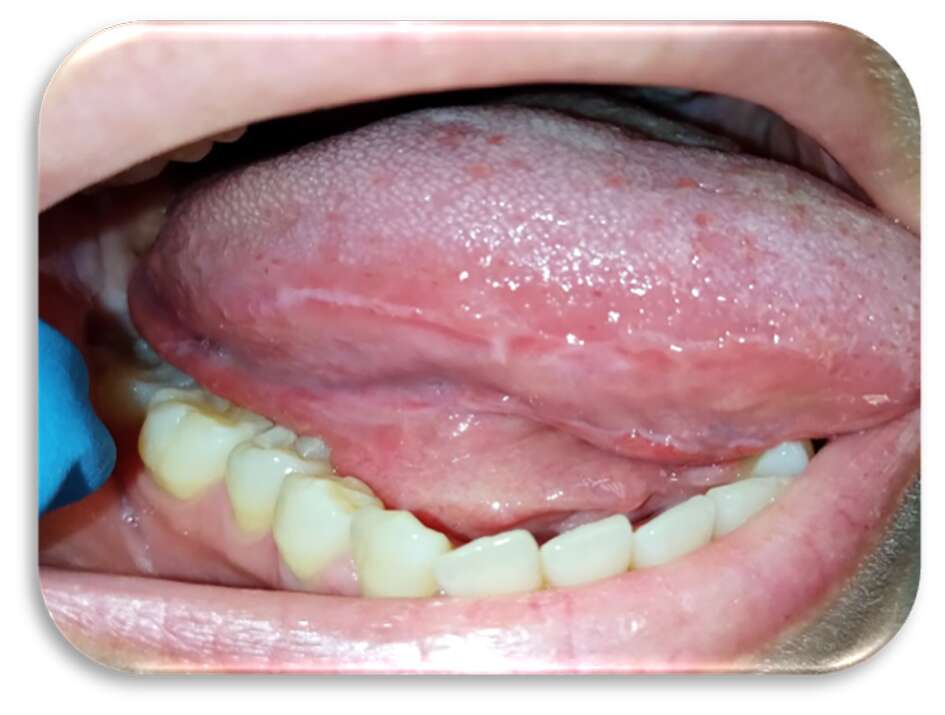

Al quarto giorno di applicazione, la paziente riportava un notevole miglioramento sintomatologico. A sette giorni c’era stata una regressione completa delle lesioni (Figure 5-6), con mucosa integra e normocromatica dove residuava linea alba a livello genieno e linguale (Figure 7-8), per la quale era stato consigliato alla paziente l’uso di un bite inferiore in resina morbida per evitare ulteriori traumi ai tessuti molli.